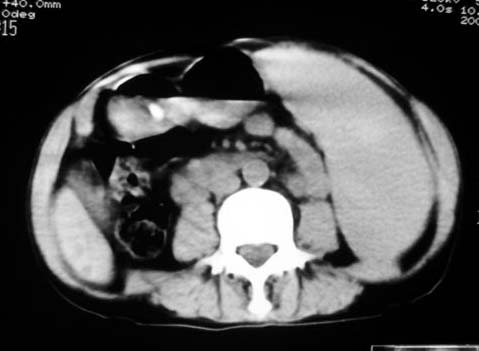

以下是引用dyqct在2007-4-20 16:38:00的发言:[br]考虑:1、巨脾;[br] 2、肝内多发低密度,首先考虑转移瘤;[br] 3、胆囊多发结石。

以下是引用andymaomao在2007-4-20 16:47:00的发言:[br]肝脾增大,肝内胆管扩张,且可见多发小囊性低密度灶,胆囊窝区高密度影,手术化疗病史,贫血....[br]1.肝脾大及贫血与术后化、药疗有关;[br]2.胆囊窝区高密度影,术后改变?肝内胆管扩张,积液?[br]3.肝内多发低密度灶,性质?建交增强